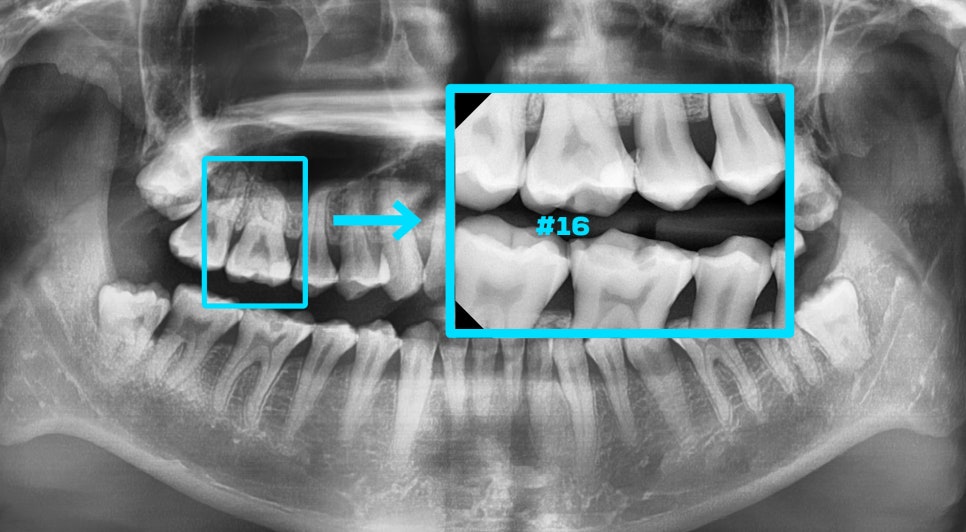

깨진 틈 사이로 이물질이나

외부 세균들이 침투하여

치수 부근까지 감염이 되어있는 것을

확인할 수 있었습니다.

아무래도 이 환자께서는

이미 치수 부근으로 병소가 퍼져 있었는데요.